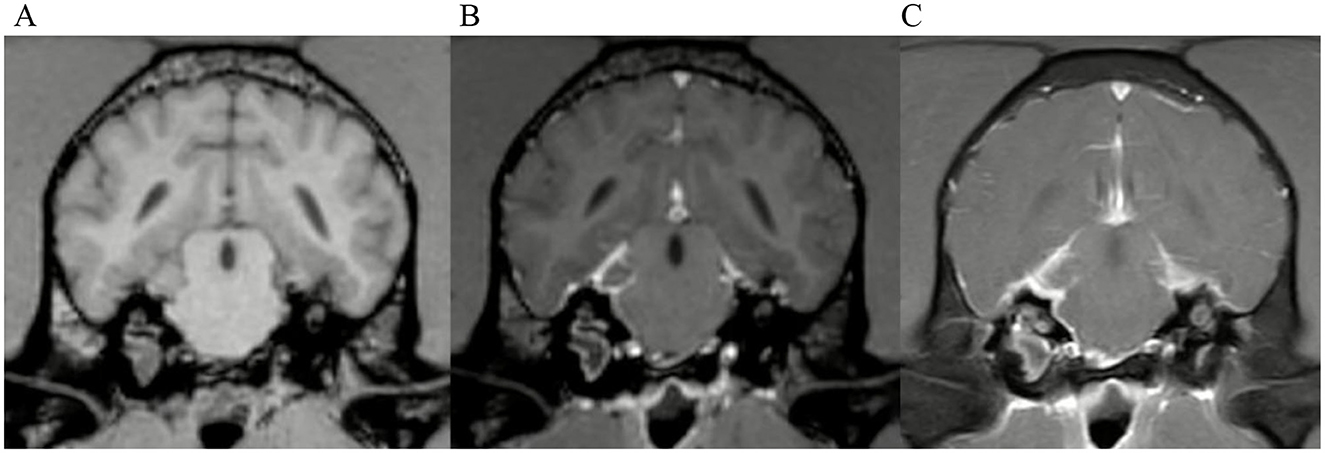

Examples of some of these cases can be found in Figures 3, 4. Meningeal enhancement was graded as focal and mild in both examples by 3 observers, while one observer graded the enhancement as focal and moderate (Figure 4). An example where no inter-observer agreement was reached can be found in Figure 5.

Figure 3. Transverse images at the level of the tympanic bullae. Example of perfect inter-observer agreement in the FS-TSE-T1W sequence in a cat. (A) is the T1W-pre-contrast image. 5/5 observers did not detect meningeal enhancement in the 3D-GRE-T1W (B), but agreed on detection in the FS-TSE-T1W (C). Meningeal enhancement was graded as focal and mild by all observers.

Figure 4. Transverse images at the level of the tympanic bullae. Example of perfect inter-observer agreement in the FS-TSE-T1W sequence in another cat. (A) is the T1W-pre-contrast image. 4/4 observers did not detect meningeal enhancement in the 3D-GRE-T1W (B), but agreed on detection in the FS-TSE-T1W (C). 3 observers graded it as focal and mild, while 1 observer graded it as focal and moderate enhancement.

Figure 5. Transverse images at the level of the tympanic bullae. Example of a case where no inter-observer agreement was reached. (A) is the T1W-pre-contrast image. 1 of 5 observers did not interpret the 3D-GRE-T1W (B) as positive for meningeal enhancement but did interpret the FS-TSE-T1W sequence (C) as positive. No other observer detected meningeal enhancement in this case of a dog.